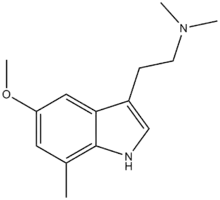

Substituted tryptamines, or serotonin analogues, are organic compounds which may be thought of as being derived from tryptamine itself. The molecular structures of all tryptamines contain an indole ring, joined to an amino (NH2) group via an ethyl (−CH2–CH2−) sidechain. In substituted tryptamines, the indole ring, sidechain, and/or amino group are modified by substituting another group for one of the hydrogen (H) atoms.

| Chemical structure | Short Name | Origin | Ring Substitution | RN1 | RN2 | Full Name | CAS Number |

|---|---|---|---|---|---|---|---|